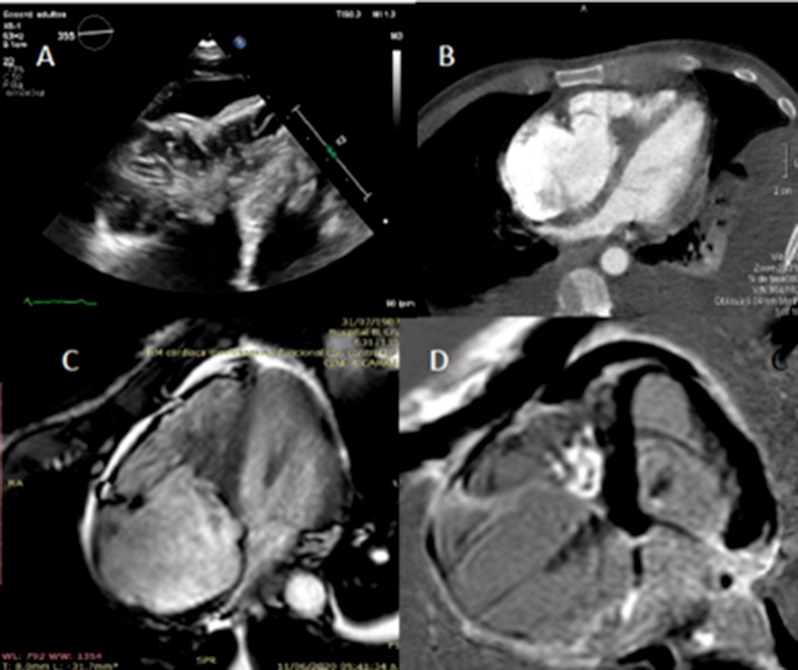

En el ecocardiograma transtorácico (ETT) se visualizó una masa ocupante medioventricular derecha con bordes irregulares y de ecogenicidad heterogénea, que comprometía el aparato subvalvular tricuspídeo y provocaba retracción focal miocárdica de la pared libre del VD y de la valva septal de la tricúspide, con insuficiencia valvular moderada excéntrica secundaria. No presentaba signos indirectos de hipertensión pulmonar. (Fig. 1)

La tomografía cardíaca (TC) descartó la presencia de trombos asociados a esa estructura y la resonancia cardíaca (RC) confirmó los hallazgos antes descriptos, descartó la vascularización de la misma y evidenció la presencia de realce tardío en su interior.